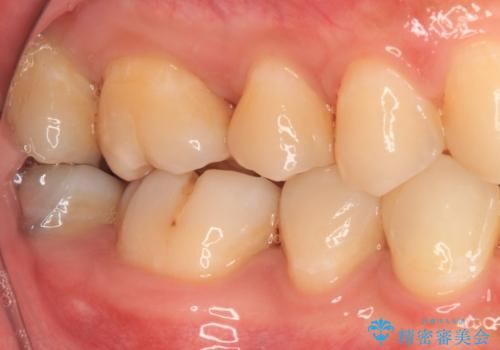

- 奥歯に頻繁に物が挟まるとのことで来院された患者様です。

最近ものが挟まりやすくなったり、冷たいものがしみるようになったりといった症状があり、診査したところ、むし歯や歯質の欠損、不適修復物などが認められました。

精度の高いセラミックインレーによる修復治療を行うこととしました。